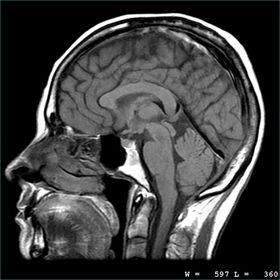

What is an MRI scan? Magnetic Resonance Imaging Relies on some molecules (protons) acting as mini magnets when places in strong magnetic field. When stimulated with radio waves they emit signals. Signals differ from each type of tissue.

What are the positives of an MRI scan? + Provides very detailed diagnostic pictures of most of the important organs and tissues in your body, enormous anatomical detail. + Can be repeated